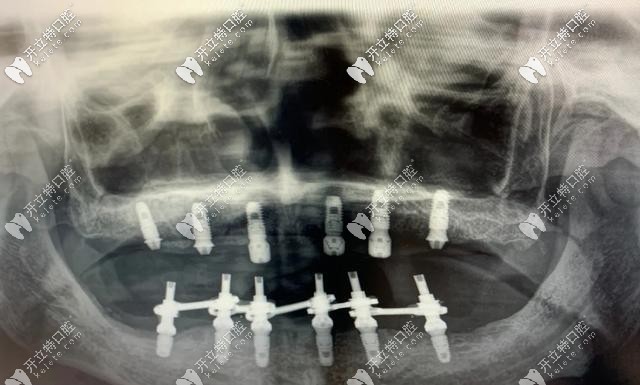

即刻負重種植牙主要針對全口無牙頜或半口無牙的情況下,每個半頜4-6顆種植牙就可以恢復半口的牙齒,術后2個小時即可戴牙進食,實現(xiàn)了當天種當天用。

即刻負重種植牙對骨質(zhì)要求比較高,牙槽骨骨量得充足,種植體長度大于10mm,直徑大于3.5mm,一般單顆牙缺失不適合即刻負重,適用于口內(nèi)多顆或全部牙齒缺失的人群。